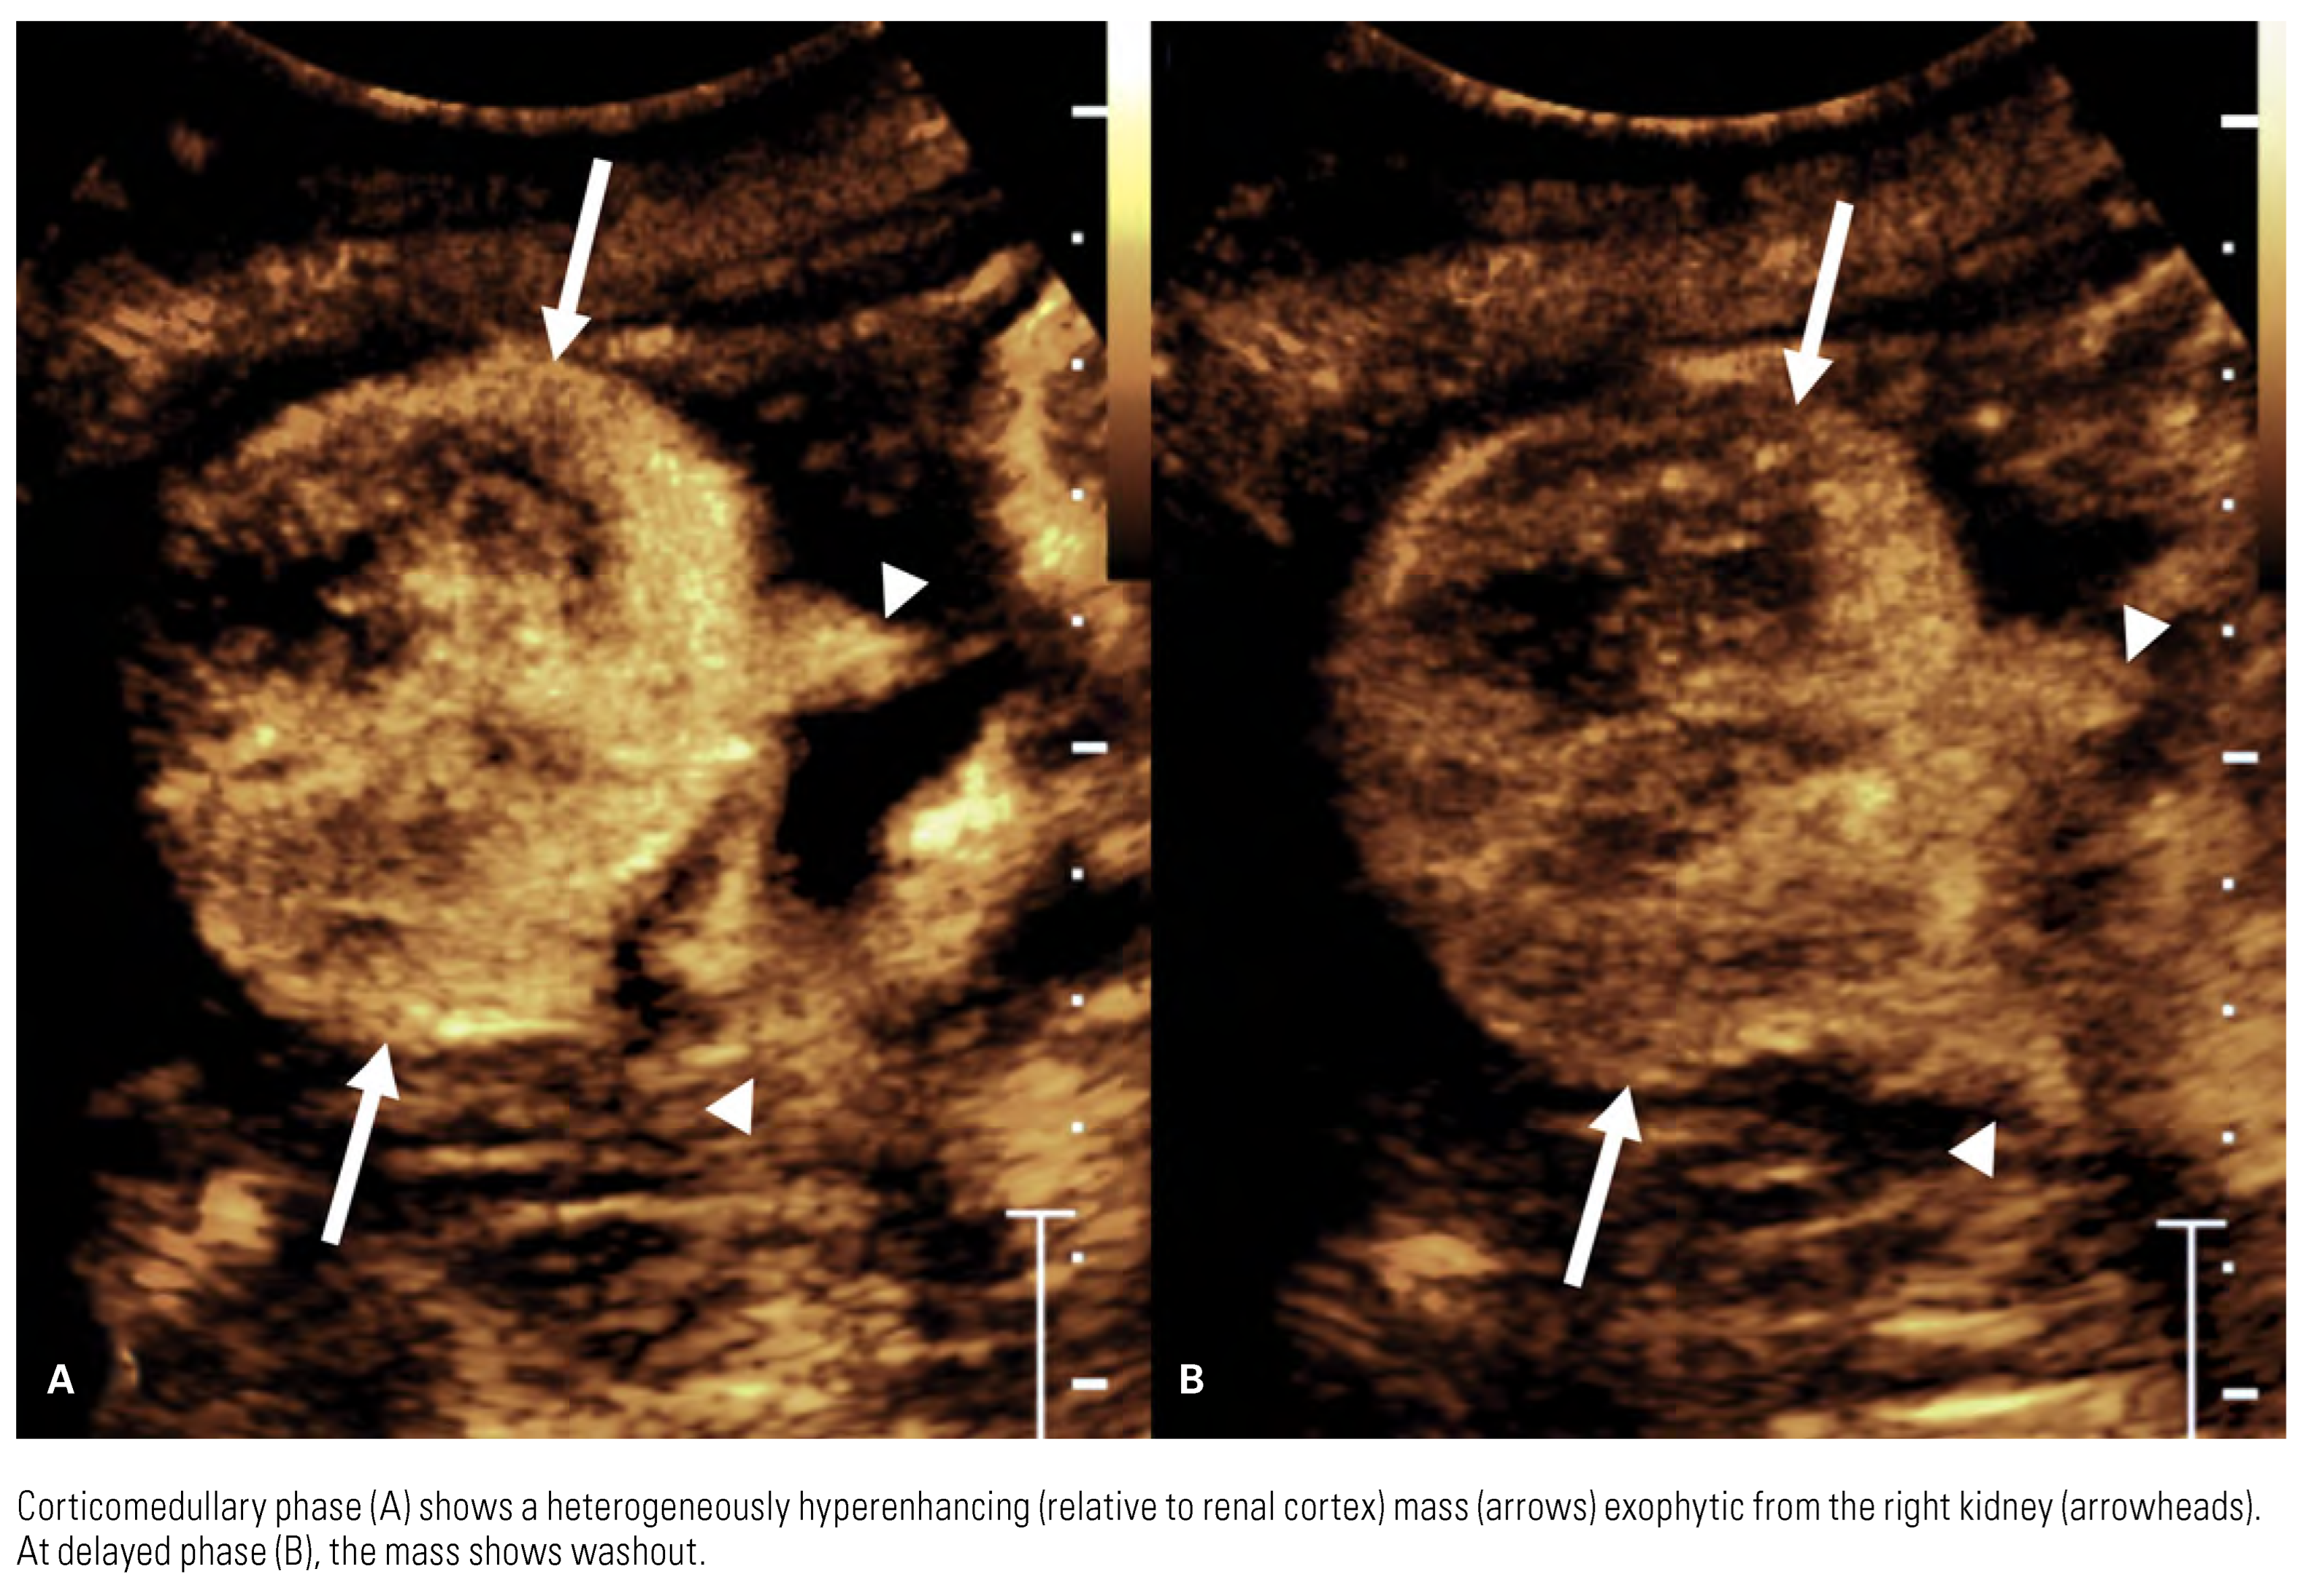

Detection and Diagnosis

Clear Cell Renal Cell Carcinom